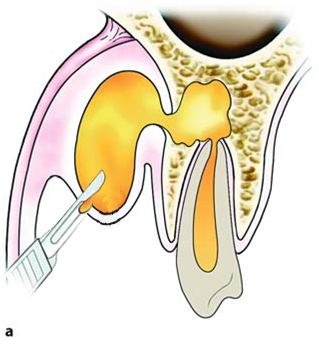

Sublingual abscess |

Palatal abscess |